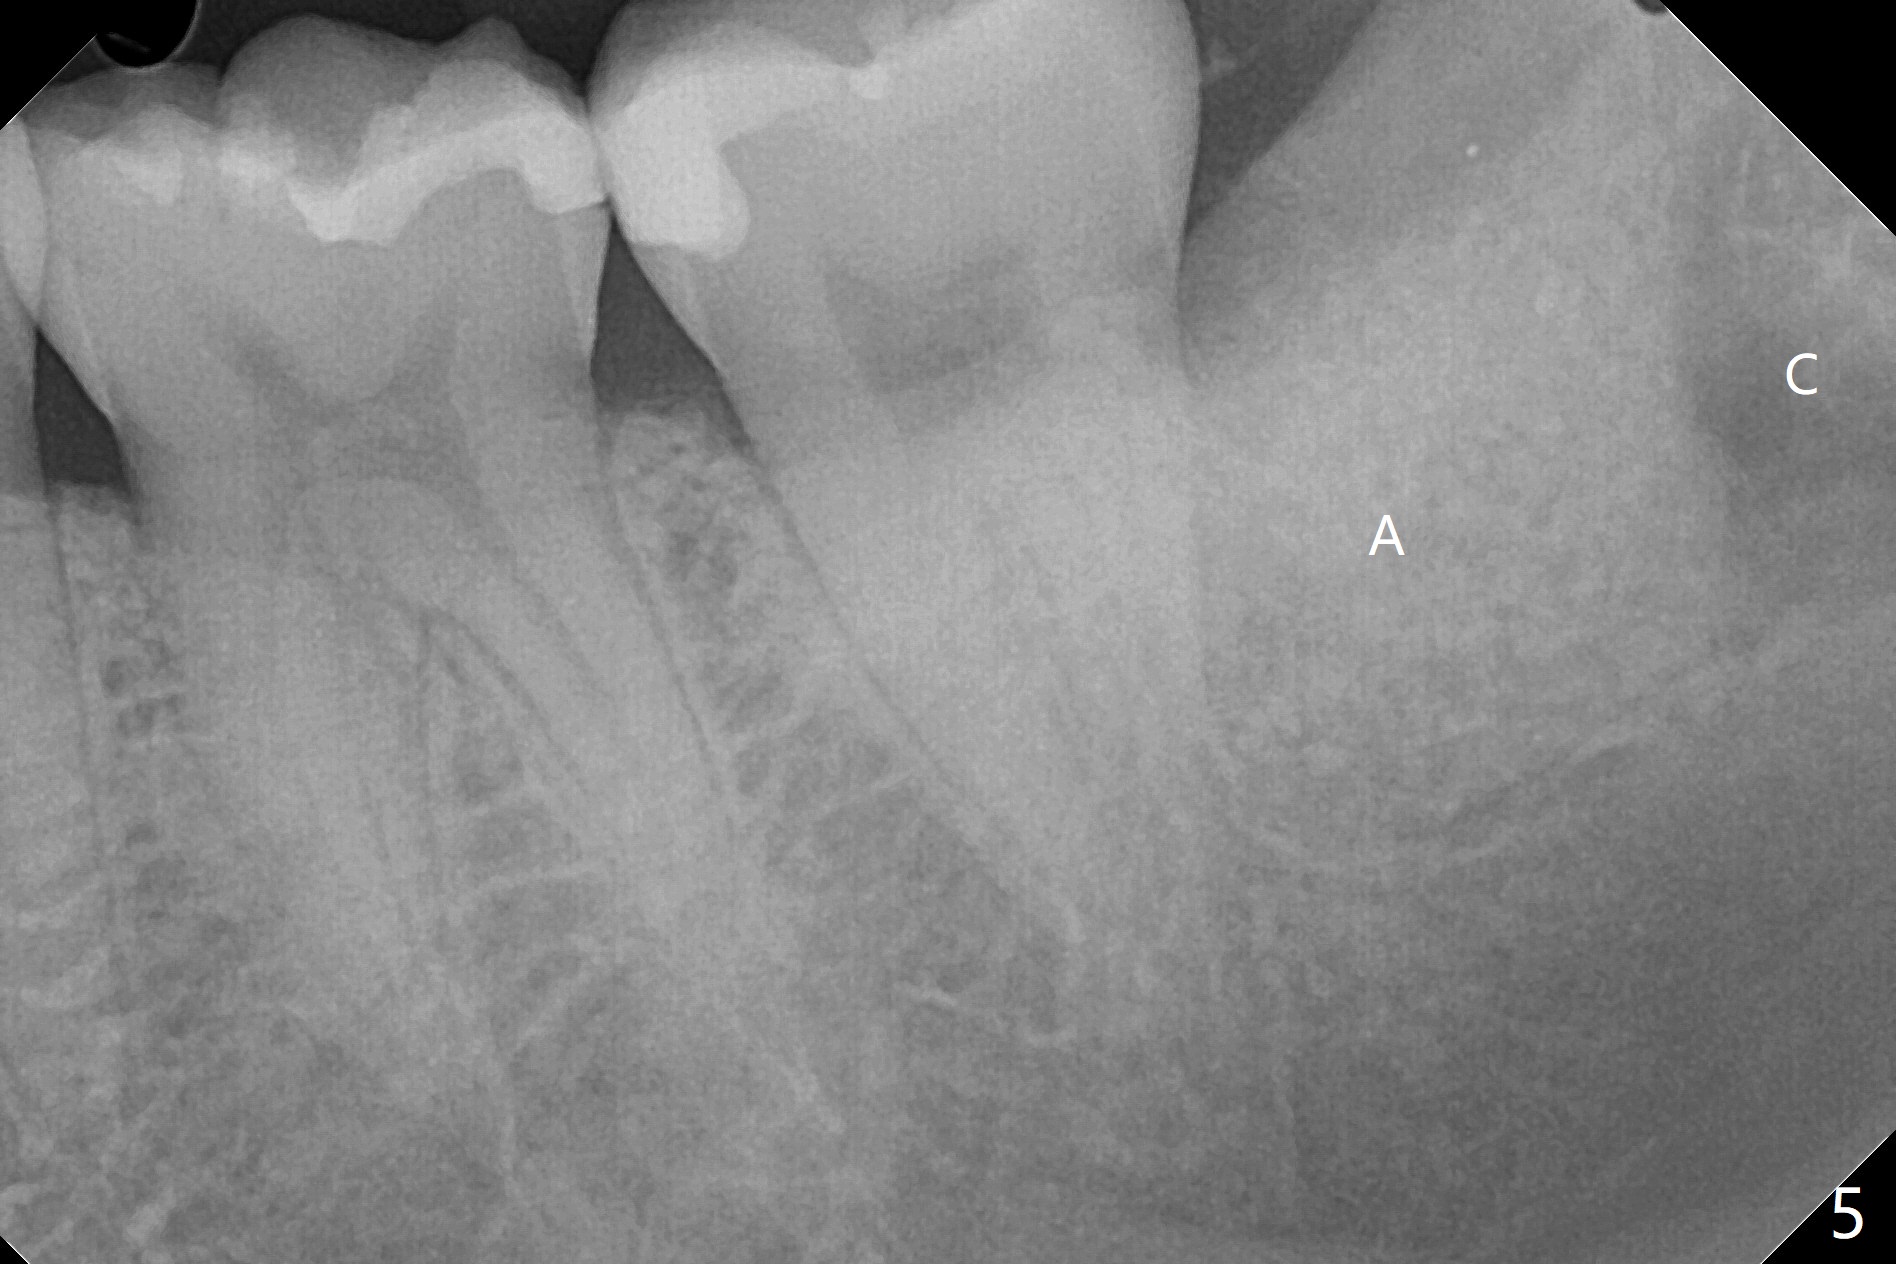

A 27-year-old woman (nervous) is going to return for #16 and 17 extraction (Fig.1). Offer sedative (Valium) if she cannot overcome fear. Take PAs for #17 and 32 to confirm Buccal Impaction, which dictates position of the accessory incision to reduce loss of bone graft in case of wound dehiscence. Place Collagen Plug (1/2 piece) in the apical portion of the sockets of the lower 3rd molars, while Augma and Osteogen Plug (1 piece) in the coronal half of #17 and 32, respectively. Place additional Collagen Plug for the remaining socket if needed before 4-0 PGA suturing as the 2nd step to decrease the chance of losing bone cement. Preop PA shows that the tooth #17 seems to be mesial (Fig.2 arrow). The accessory incision is placed mesiobuccal of the tooth #18 (Fig.4 red oblique line, Fig.6) so that it is not overlying the bony defect (Fig.4 arrowheads). Since the access to the impacted tooth is limited, small field of CT is taken (Fig.3,4), which shows the root is yet to be exposed (Fig.3 R). After tooth removal, Collagen plug is placed in the apex of the socket for hemostasis (Fig.5 C), while Bond Apatite coronal for bone regrowth (A). There is no dehiscence 11 days postop (Fig.7), although the patient complains of pain in the jaw and the temporomandibular region. The anterior portion of the external oblique ridge forms 1 year 7 months postop (Fig.8).